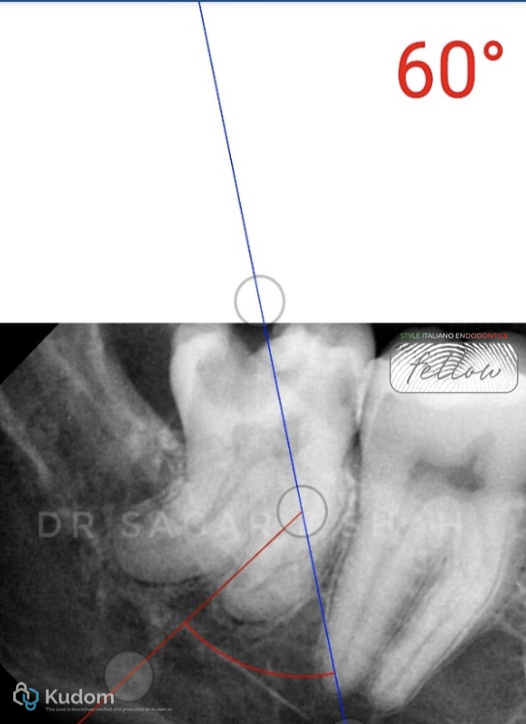

PREOPERATIVE ASSESSMENT:

Mesial canal curvature- 60 degree

The radius of curvature- 14 mm

Close proximity to the mandibular canal.

Pulp calcification was seen with the distal root.

AAE DIFFICULTY ASSESSMENT- HIGH